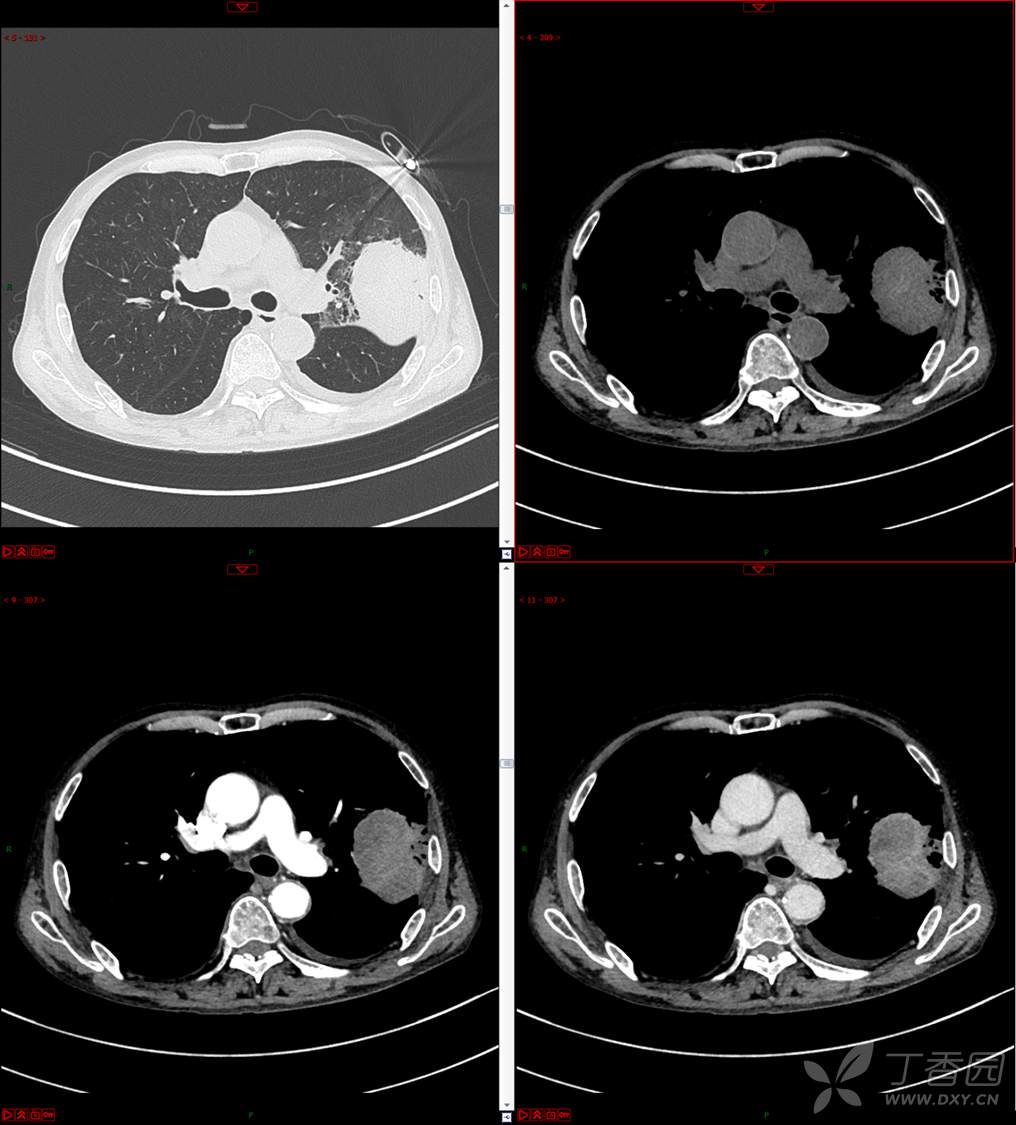

现病史:患者自诉5月前无明显原因及诱因出现纳差、乏力,伴进食后腹胀,无腹痛、腹泻、发热、盗汗、恶心、胸闷,未行特殊处理。1月前无明显原因诱因出现咳嗽,呈阵发性,咳白痰,痰中带鲜红色血丝,10余口/日,无血块,仍伴纳差、乏力、进食后腹胀,无恶心、呕吐、呕血,无头晕、心慌、喘憋、胸闷。在家未行特殊治疗,来我院就诊,2022.8.18行胸部(肺)CT平扫:左上肺占位并左侧肋骨骨质破坏,考虑间叶源性恶性肿瘤。门诊以“肺肿物”收入我科。患者自发病以来,神志清,精神可,饮食差,睡眠可,二便正常,近3月减轻5Kg。